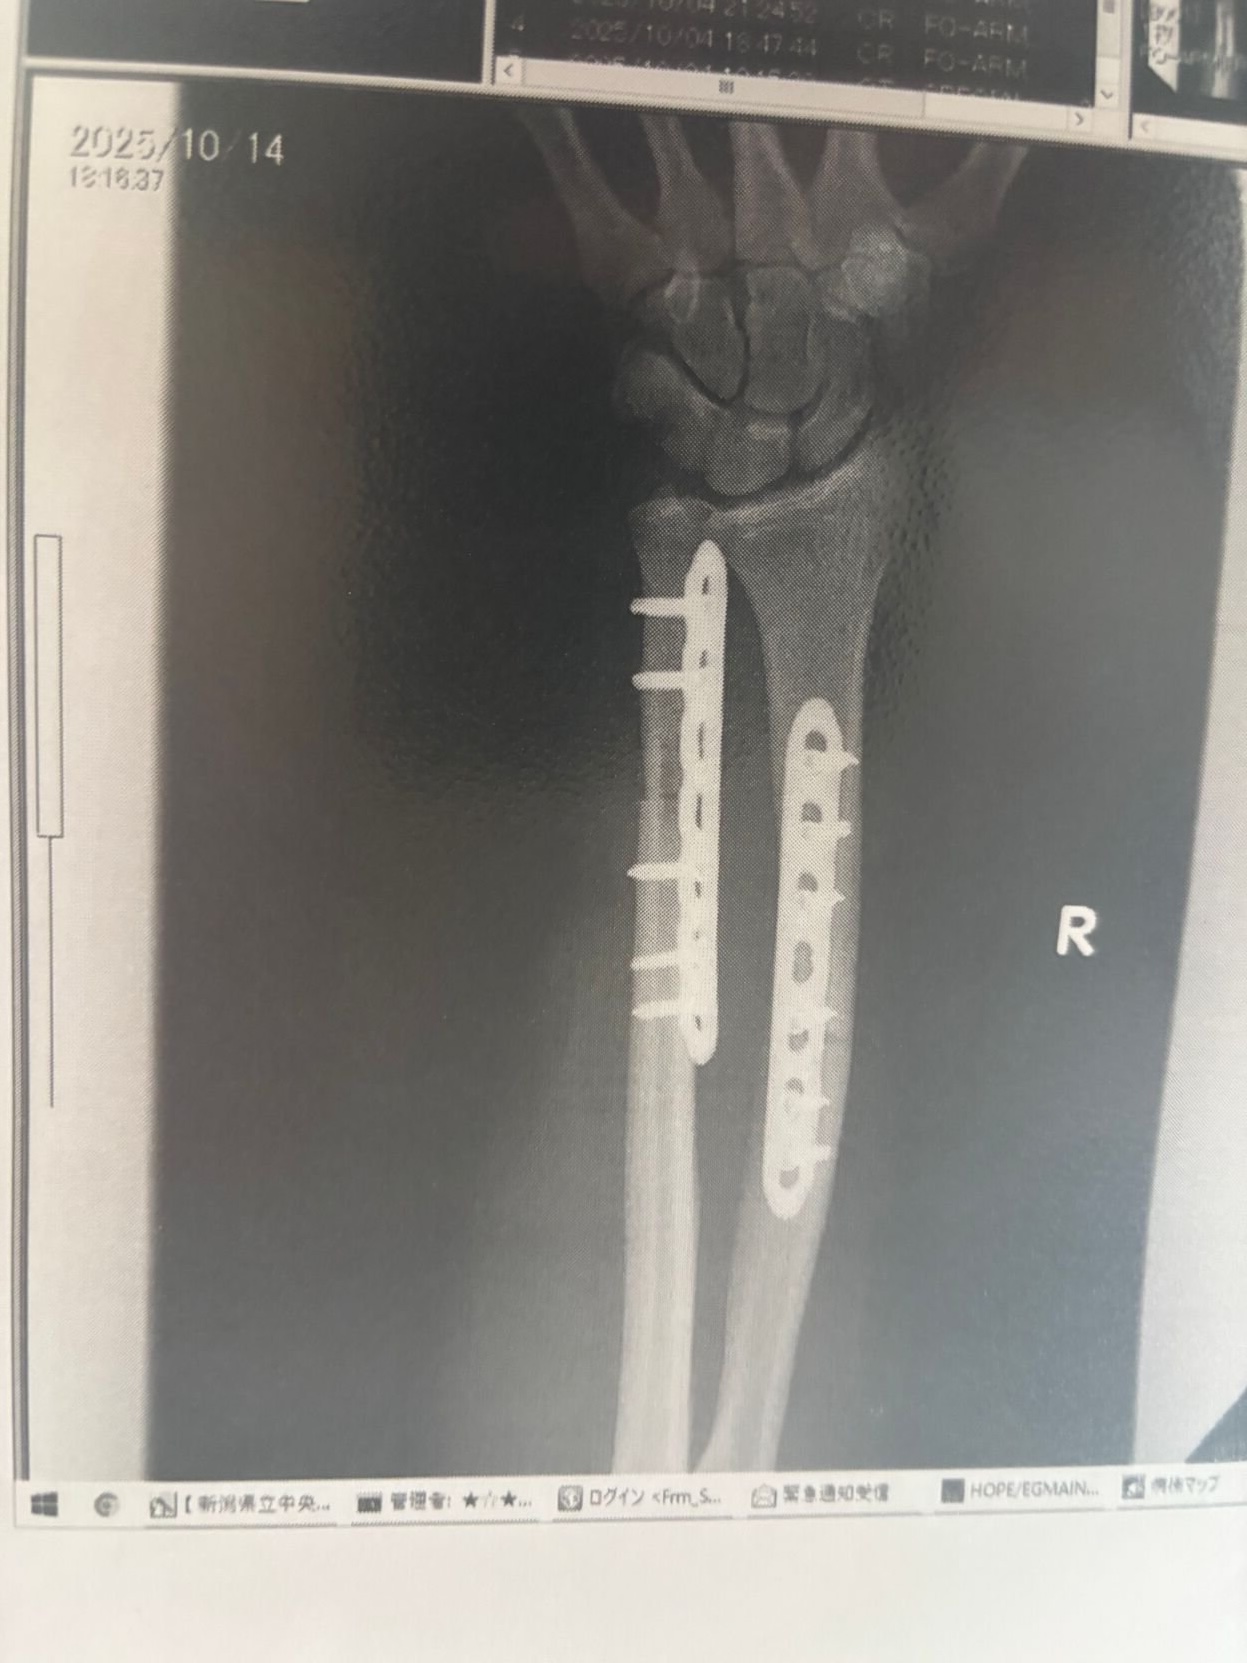

Halloran 目前仍在醫院康復。他透露,過去兩週已接受三次手術,包括在手臂植入金屬板,以及一次髖骨移植,用以修補手臂上被咬掉的一塊骨頭。他坦言,將面臨漫長的物理治療及康復之路,雖然仍計劃重返超級馬拉松訓練,但也明白情況與以往不同。他將這次襲擊留下的心理創傷,比喻為「被鯊魚攻擊過的人試圖回去衝浪」。